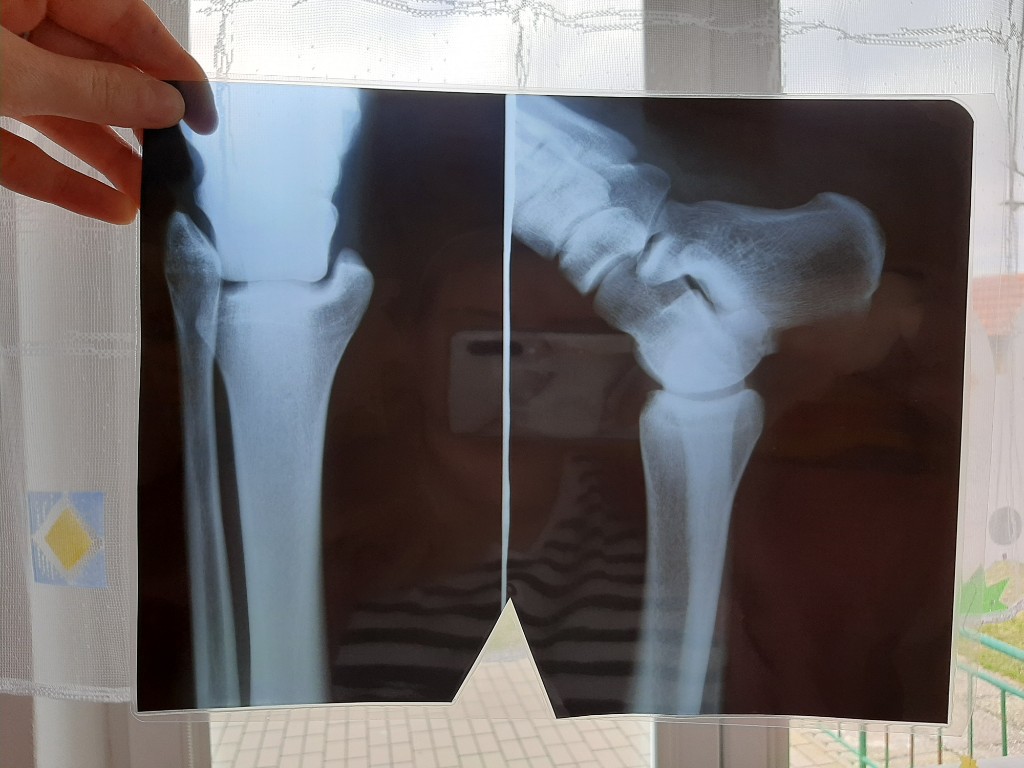

První pomoc v MŠ

Datum: 22. 4. 2022 | Počet fotografií: 279